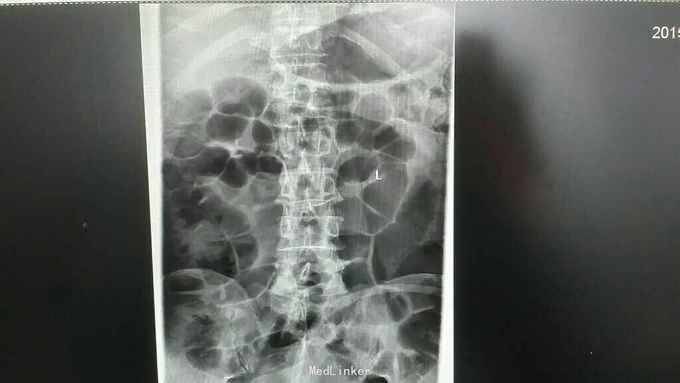

查体:脊柱生理曲度存在,无明显前凸,侧弯或后凸畸形,约胸10至腰5节段压痛及叩击痛阳性,双下肢肌张力正常,双侧股四头肌肌力约三级,双侧足背伸肌,踇背伸肌肌力约四级,双侧“4”字试验阴性,双侧直腿抬高试验阴性。肛周约15cm范围皮肤感觉减退。 辅助检查:肿瘤标志物无明显异常,血沉达120mm/h,血红蛋白111g/l,球蛋白与白蛋白比值倒置,血免疫球蛋白IgG达46.2g/l,明显升高。血清Kappa轻链与血清Lambda轻链比值明显升高。余辅助检查见下图。

通过影像学,实验室检查,骨髓穿刺检查及行CT引导下穿刺病理结果,患者多发性骨髓瘤诊断已明确。于全麻下行“腰1椎体病理性骨折病变清除减压内固定术”,术中可见病变压迫脊髓明显,彻底减压,术中出血较多,椎体破坏较重,未予骨水泥塑型,术后患者症状缓解明显,拆线后转至血液科进一步治疗。

多发性骨髓瘤是一种单克隆的浆细胞异常增生所致的恶性肿瘤,常以骨骼症状为首发,以脊柱最常累及,本例患者主要手术指征为持续且无法缓解的骨痛,并存在脊髓和神经根压迫症状,,主要影像学表现为穿凿样溶骨性改变,周围无硬化改变。很多全身骨现象无明显的阳性表现,增加了诊断的难度,上面提到的血沉升高,贫血,球白比倒置,血免疫球蛋白升高,骨髓穿刺综合判断,诊断明确后,一般行姑息性手术治疗,一般预后较差,随访见到生存期最长为4年。